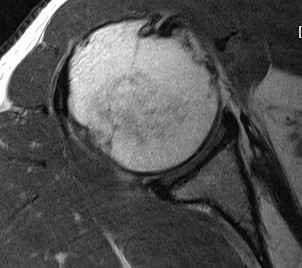

Full thickness retracted subscapularis tear